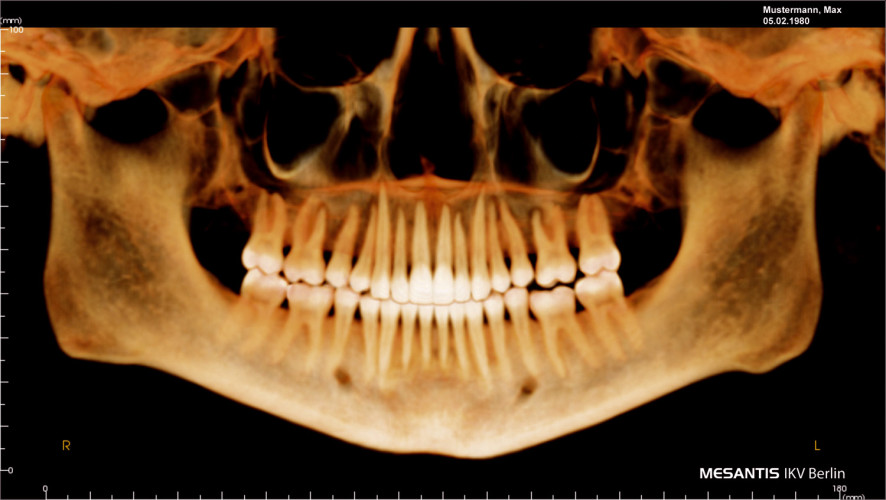

Abb. 3:  Panoramaansicht, die aus einem DVT generiert wurde. Aufgrund der Patientendaten (oben rechts) darf diese Aufnahme datenschutzrechtlich nicht per E-Mail unverschlüsselt versendet werden. Abb. 4: Typische Darstellung des Schädels von lateral mit Überlagerung der oberen Atemwege. Aufgrund der sogenannten „Clipping-Funktion“ (Darstellung dünnster Schichten ohne Überlagerungen) können Messpunkte für 2-D- bzw. 3-D-Analysen viel genauer bestimmt werden als bei herkömmlichen Fernröntgenaufnahmen. Auch diese Aufnahme darf nicht unverschlüsselt versendet werden.	(Fotos: MESANTIS IKV Berlin)